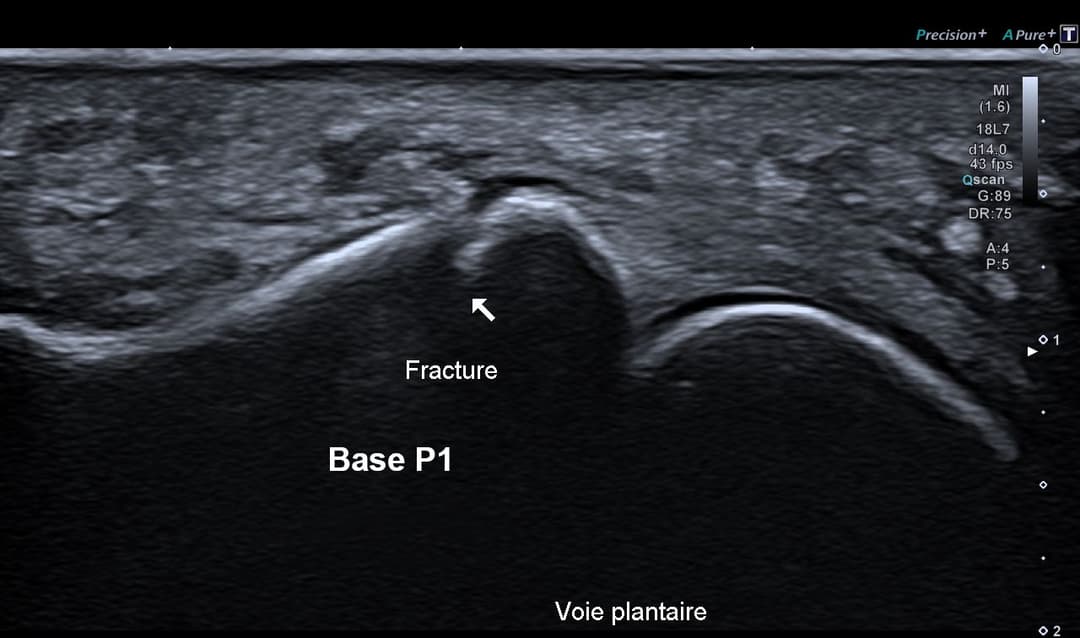

Échographie

Fracture instable étudiée en échographie dynamique

L'échographie permet de rattraper des radiographies interprétées initialement comme normale, en explorant finement via une échopalpation de la zone douloureuse la corticale osseuse.